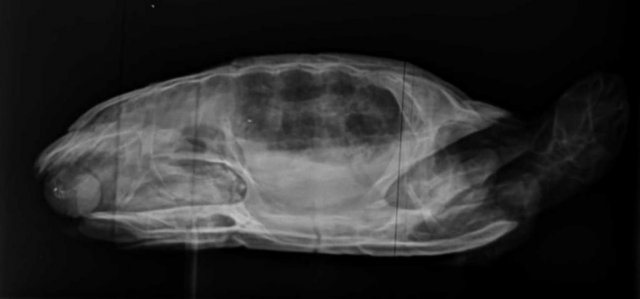

Алексей Alex-Raduga Ваше имя: Алексей Локация: Россия, МО, Серпуховский район Опубликовано: 31 января 2024 Автор Опубликовано: 31 января 2024 @moth здравствуйте ! Сегодня возил на рентген, сделали все проекции, Савина сказала - возможно пневмония, назначила антибиотик энрофлоксацин 2,5%, по 0,12мл 3-4 раза через день и элеовит 0,18мл. - 2 раза с интервалом в 14 дней. Также остается эспусмизан еще 14-21 день (21 день уже его давал, с кормом раз в 3 дня). Также назначила взять анализ кала. Если не пройдет - сказала везти на КТ. Все верно, больше ничего пока не нужно ?

Консультанты moth Ваше имя: Мария Локация: Москва Опубликовано: 31 января 2024 Консультанты Опубликовано: 31 января 2024 @Алексей Alex-Raduga да, всё верно одно лёгкое мутное совсем, жалко тогда она не стала другие проекции делать. А Элеовит ему делали раньше?

Консультанты moth Ваше имя: Мария Локация: Москва Опубликовано: 8 февраля 2024 Консультанты Опубликовано: 8 февраля 2024 @Алексей Alex-Raduga она сказала, что тут однозначно кт нужно. Либо лёгкое схлопнулось, либо сильная односторонняя пневмония. Трава с мостика такое бы не вызвала.

Алексей Alex-Raduga Ваше имя: Алексей Локация: Россия, МО, Серпуховский район Опубликовано: 15 февраля 2024 Автор Опубликовано: 15 февраля 2024 (изменено) Результаты Кт : Протокол КТ Информация по животному Тотоша ,рептилия ,Черепаха красноухая. Протокол ДЫХАТЕЛЬНЫЕ ПУТИ - Визуализируется короткая трахея, разделяющаяся на два бронха, делающие изгиб в дорсальном направлении и входящие в легкие. Правое легкое имеет типичный сегментированный многокамерный вид, пневматизировано, имеет ретикулярный и "сотовый" рисунок, определяется умеренное утолщение перегородок. Бронх левого легкого частично пневматизирован, на остальном протяжении заполнен мягкотканым патологическим содержимым. Левое легкое уменьшено (25х16х12 мм), безвоздушно, паренхима уплотнена до мягкотканых значений, перфузия сохранена, слабо неравномерная. КОСТНЫЕ СТРУКТУРЫ - без патологических изменений. СЕРДЦЕ - без патологических изменений. ПЕЧЕНЬ - без патологических изменений. ЖЕЛЧНЫЙ ПУЗЫРЬ - в правой доле печени, грушевидной формы, умеренно наполнен однородным жидкостным содержимым. СЕЛЕЗЕНКА - овальной формы, 12 мм, расположена дорсо-медиально от желудка. ПОДЖЕЛУДОЧНАЯ ЖЕЛЕЗА - не визуализируется. ЖЕЛУДОК - не наполнен, стенки не утолщены. КИШЕЧНИК - содержит минимальное количество химуса и газ, стенки не утолщены. ПОЧКИ - локализованы в дорсальной части каудального целома, структура и перфузия не изменены. МОЧЕВОЙ ПУЗЫРЬ - умеренно наполнен, стенки не изменены. ПОЛОВЫЕ ОРГАНЫ - не визуализируются. Заключение Заключение: КТ-признаки тотальной левосторонней пневмонии. Обструкция левого бронха. Информация по животномуТотоша ,рептилия ,Черепаха красноухая Анамнез: В мире животнрых (Серпухов) Савина Ярослава Игоревна Жалоба - в течении месяца всплывает на одну сторону (правую). Бывли в сторонней клинике - назначили антибиотик, газасвязывающий препарат, витамины. Активность - норма. Аппетит - норма. Дефекация - норма. Кормление - корм для черепах. Содержание - аквариум, вода 26-27 гр, мостик, УФ лампа и лампа нагрева. Объективно: Общее состояние - удовлетворительное на момент осмотра. Ментальный статус - ясный. Дегидратация - не выражена. Глаза - чистые. Носовые ходы - чистые. Ротовая полость - без патологий. ВСО - бледно-розовые. Состояние кожного покрова и панциря - линька. Упитанность - норма. М - 272 гр. Диагнозы: Предварительный диагноз: Пневмония Врач: Ложечко Анастасия Леонидовна А НАЗНАЧЕНИЙ НЕТ ! Чем лечить-то ? Продолжить уколы энрофлоксацина ? Изменено 15 февраля 2024 пользователем Алексей Alex-Raduga